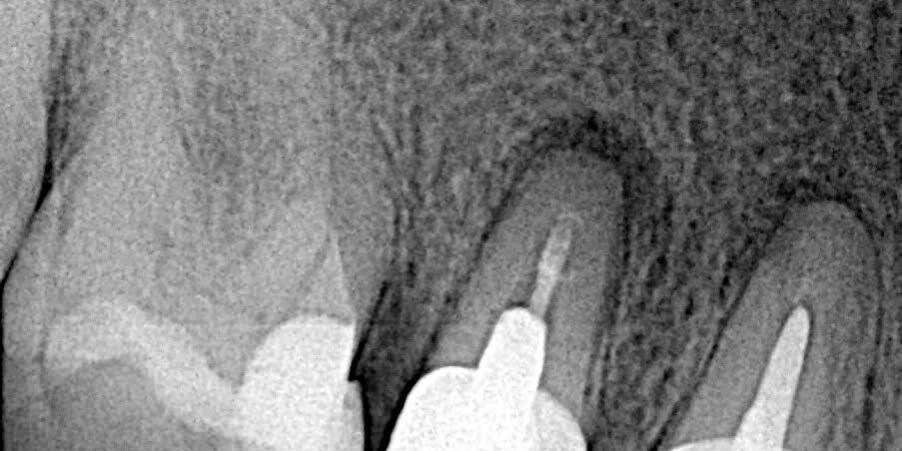

Se toma Rx periapical y se pide CBCT para planificar la cirugía paraendodóntica con obturación a retro por el alto riesgo de fractura al intentar el retiro de coronas y pernos. Presentaba sintomatología hace varios meses, dolor a la palpación de la zona y test de percusión vertical positiva.

- Rx. Previa